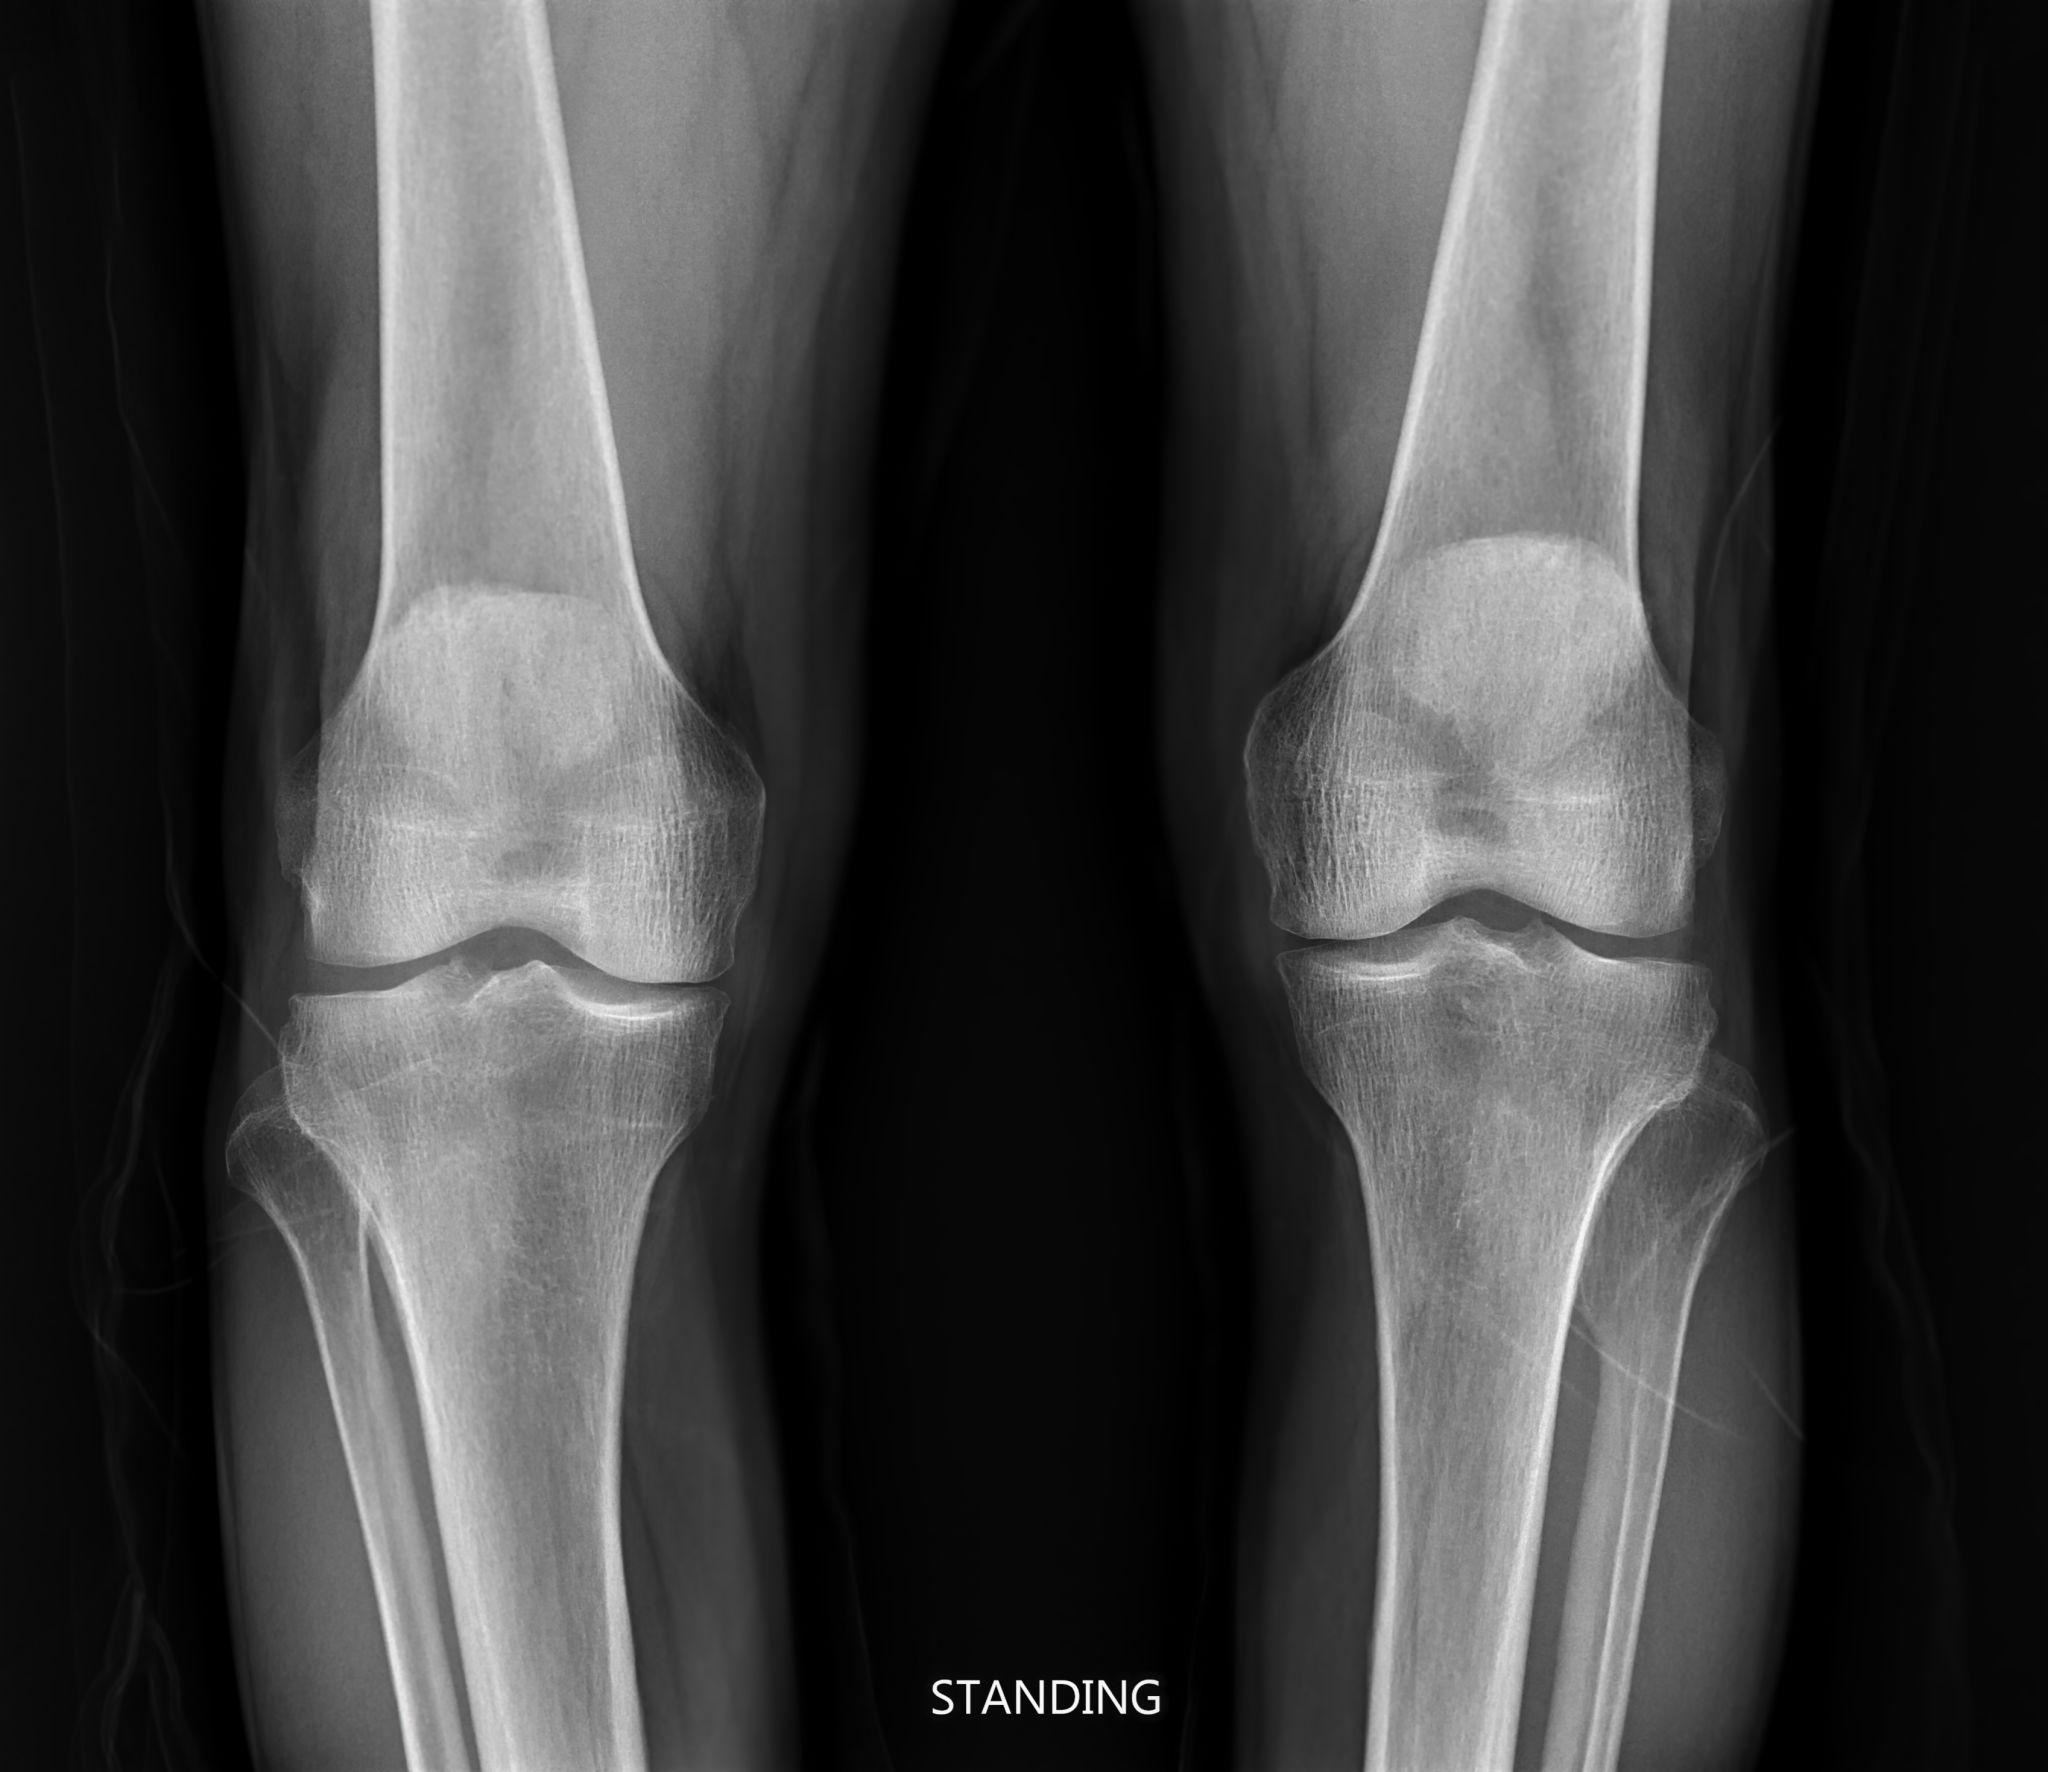

La proiezione antero-posteriore eseguita sotto carico, cioè con il paziente in piedi, rappresenta la base dello studio radiografico del ginocchio.

Questa proiezione consente di valutare:

• il compartimento mediale

• il compartimento laterale

• l’ampiezza dello spazio articolare, indicativa dello stato della cartilagine

L’esecuzione sotto carico è essenziale perché riproduce le condizioni reali in cui il ginocchio lavora nella vita quotidiana.

Una radiografia eseguita da sdraiati può infatti sottostimare il grado di usura, mostrando spazi articolari apparentemente conservati che, in realtà, si riducono significativamente quando il ginocchio è caricato.

Per questo motivo, una proiezione AP sotto carico correttamente eseguita è indispensabile per una valutazione attendibile dell’artrosi del ginocchio.

Radiografia ginocchia AP sotto carico in stazione eretta per valutazione dell’artrosi del ginocchio